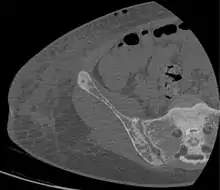

Brown tumors in the pelvis and a hip fracture.[18]